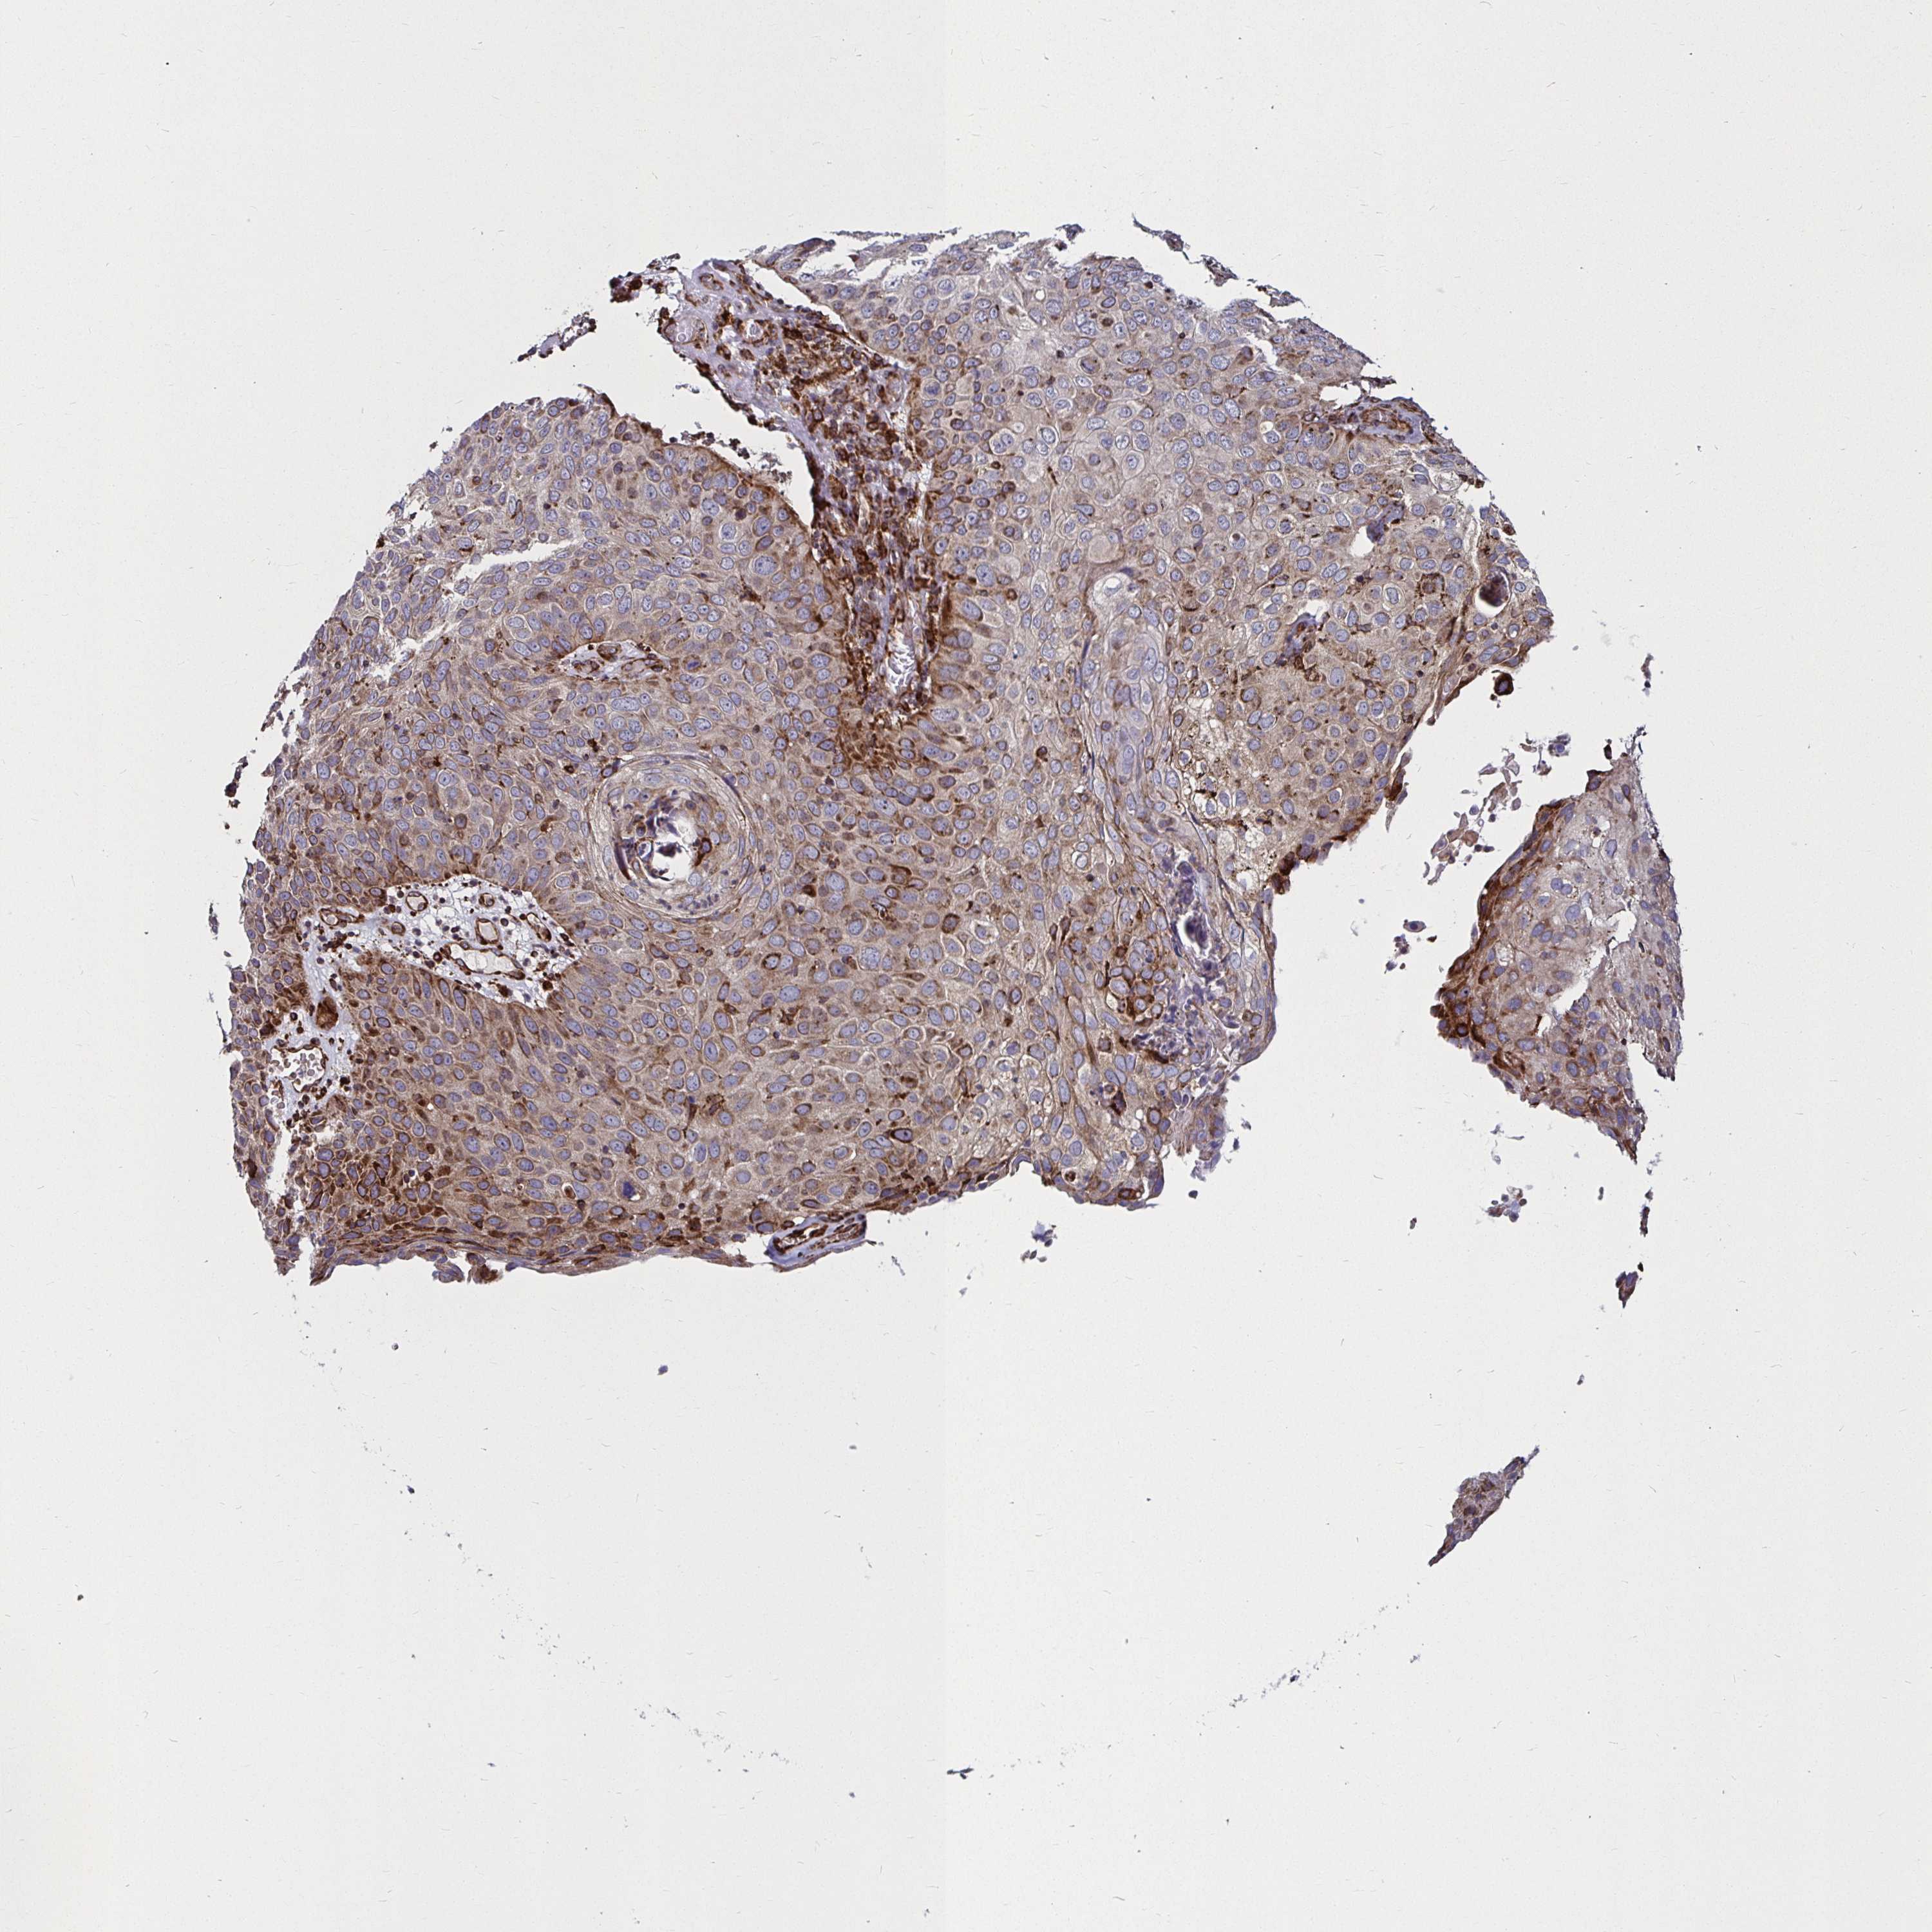

CANCER SKIN CANCER Show tissue menu

SKIN CANCER - Protein expressioni

A mouse-over function shows sample information and annotation data. Click on an image to view it in a full screen mode. Samples can be filtered based on level of antibody staining by selecting one or several of the following categories: high, medium, low and not detected. The assay and annotation is described here.

Each image is clickable and will lead to virtual microscopy that enables deeper exploration of all samples and also displays staining intensity scores, fraction scores and subcellular localization as well as patient and tissue information for each sample.

Antibody HPA045821

Antibody HPA054352

Antibody CAB012229

Basal cell carcinoma

Squamous cell carcinoma, NOS